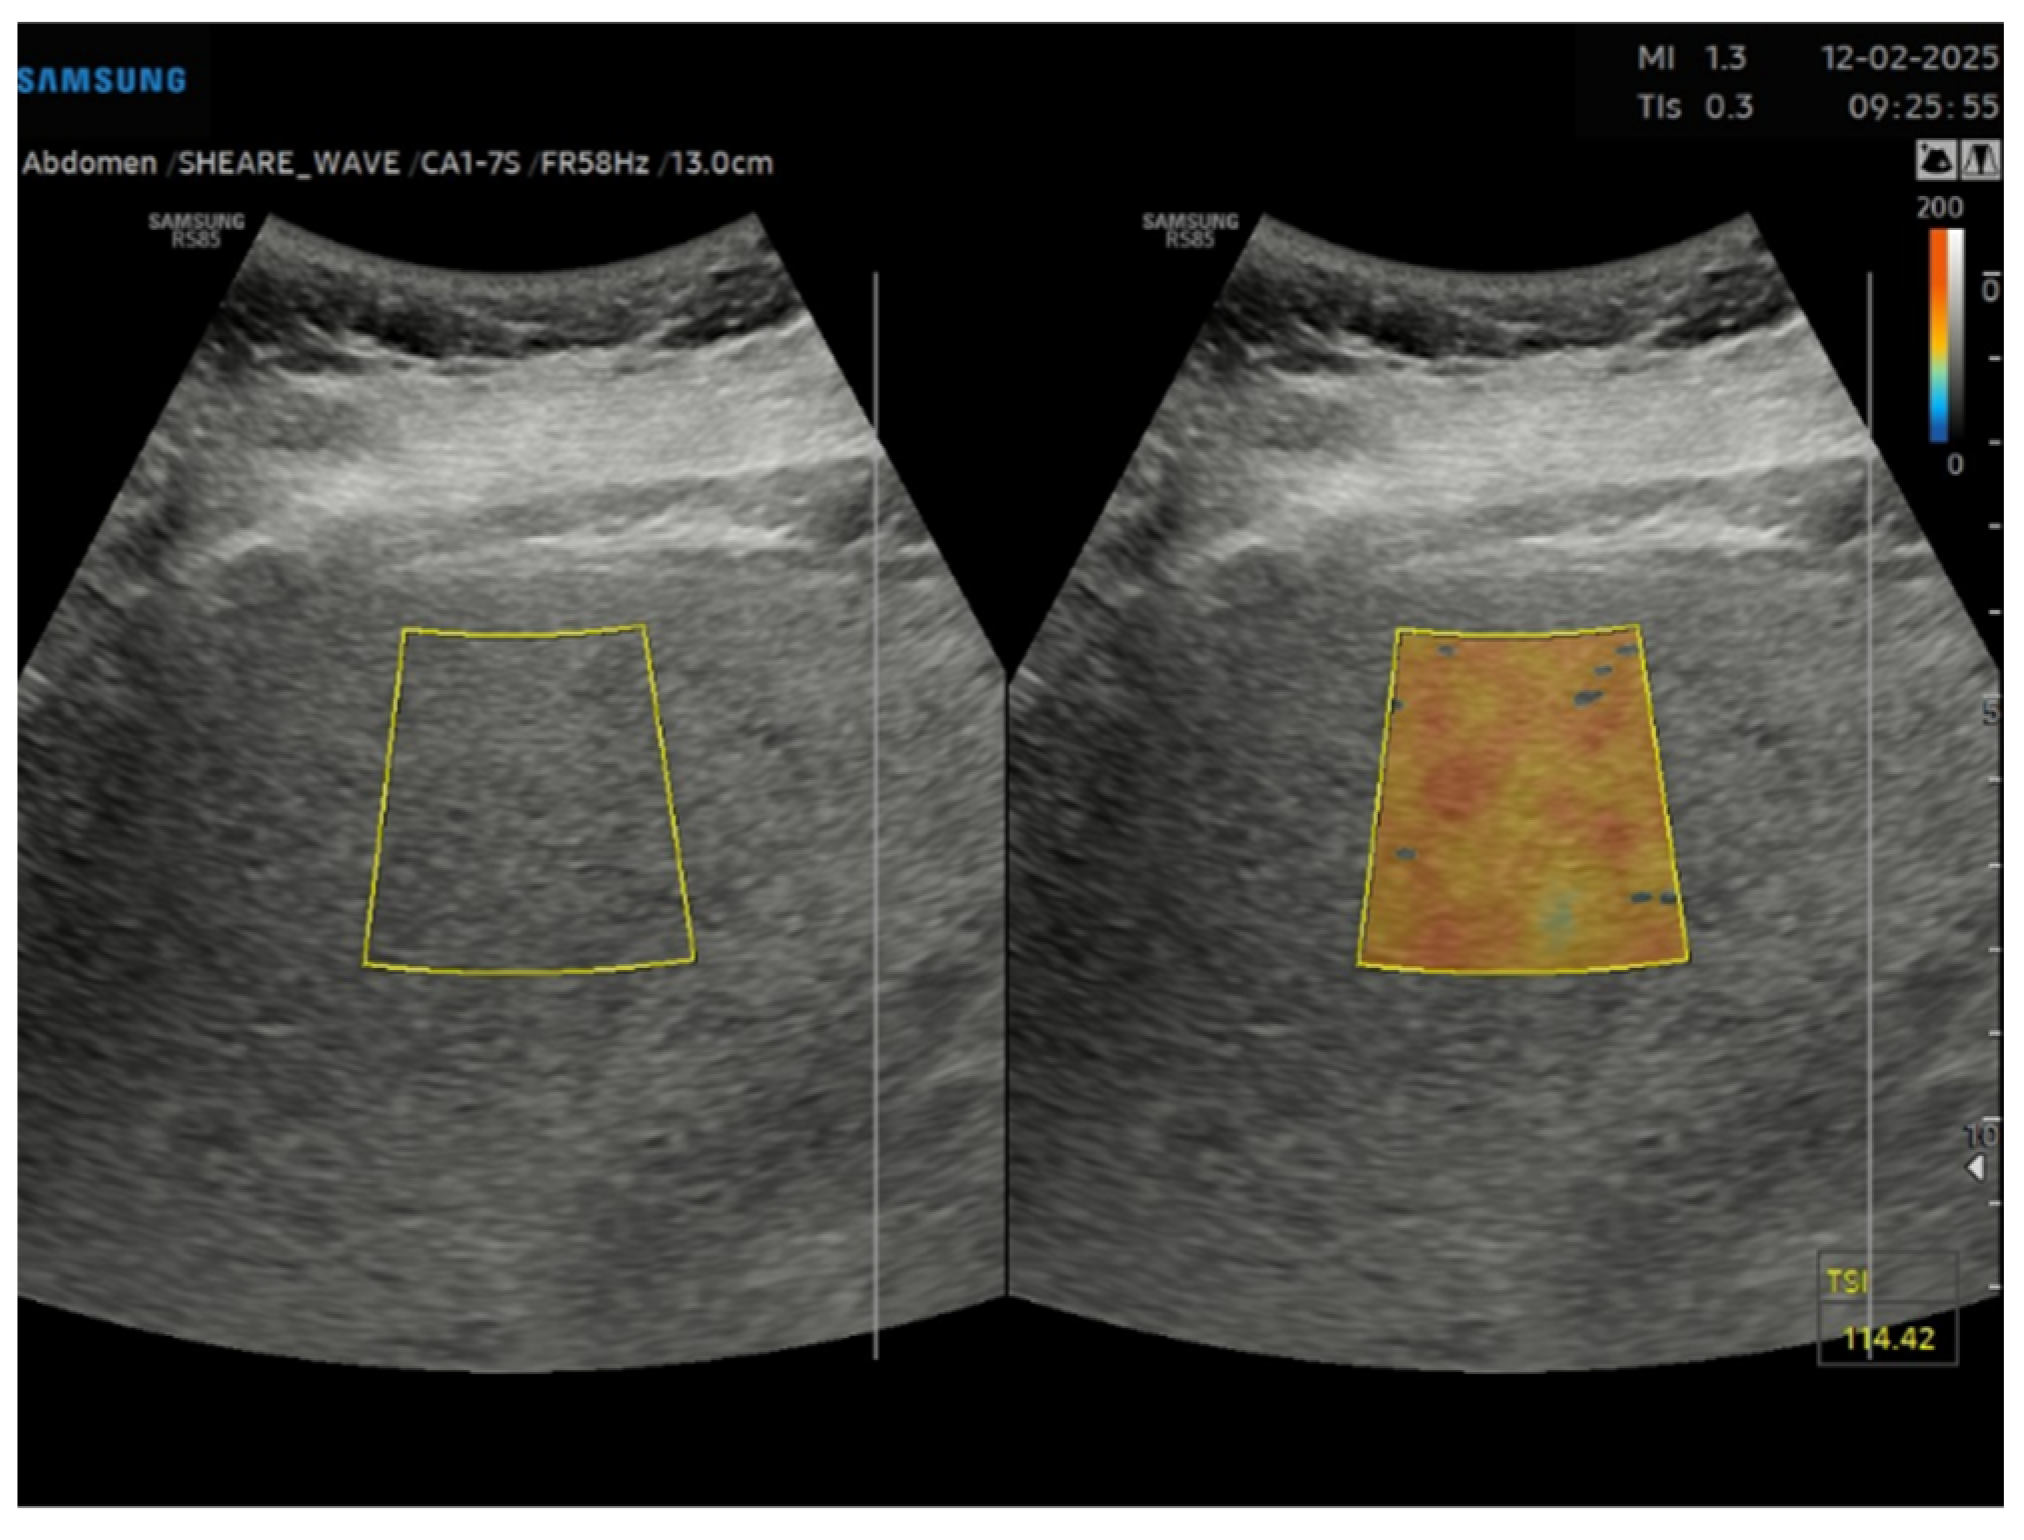

Figure 2. Tissue scatter imaging (TSI) of a liver with severe steatosis in a 51 years old female patient with grade II obesity.

Among non-invasive alternatives, magnetic resonance imaging-based proton density fat fraction (MRI-PDFF) is an accurate and reproducible method for quantifying liver fat and has been used as a reference standard in numerous clinical trials [16,17]. Despite its precision, MRI-PDFF lacks cost-effectiveness for widespread clinical use. In this context, recent studies have demonstrated promising results for detecting and grading hepatic steatosis using US and quantitative ultrasound (QUS), which combine non-invasiveness, broad availability, and cost-effectiveness [18,19]. Fat deposition alters ultrasound signals in three key ways: amplitude, frequency variation, and signal scattering. The brightness information in US images reflects a combination of these properties. Several methods have been introduced to quantify these changes and improve the diagnosis of fatty liver. One of these tools is the echogenicity ratio of the liver compared to the kidney, namely hepato-renal index (HRI). HRI has shown significant correlation with histologic steatosis. Studies have reported that HRI is highly accurate (>90%) for detecting hepatic steatosis and correlates strongly with MRI-PDFF in patients without advanced liver fibrosis [20]. Currently, several US manufacturers offer automated HRI calculation tools. In particular, Samsung offers as a quantification tool for fatty liver the EzHRI function which improves workflow by suggesting initial ROI (region of interest) positions. Moreover, other techniques used in clinical studies estimate the attenuation coefficient (AC) and the backscatter coefficient (BSC). The AC measures the loss of US energy in tissue, whereas the BSC measures the US energy reflected from tissue, which relates to tissue microstructure [21]. Samsung has integrated these methods into their US systems, proving tools like TAI (Tissue Attenuation Imaging) and TSI (Tissue Scatter Imaging). TAI quantitatively measures the attenuation of ultrasound signals received from the liver. TSI quantifies the scattered signal distribution based on backscattered signals. The combination of AC and BSC allows for the calculation of the ultrasound fat fraction (USFF), a quantitative US-based method for estimating liver fat content [22]. Several studies have shown strong agreement between USFF and MRI-PDFF measurement for quantifying liver fat content, highlighting its potential clinical utility in enhancing the diagnostic value of US for hepatic steatosis [23,24]. Despite this advancement, there is limited data regarding the clinical use of USFF, and threshold for different grades of steatosis remains undefined. Nonetheless, none of the previous study investigating the diagnostic value of the USFF, focused on the subset of obese patients, which is a major risk for evolution from MASLD to liver cirrhosis [25]. Additionally, due to the technical challenge to perform a good quality imaging in obese patients, a reliable non-invasive standard measurement of liver steatosis could be crucial [26].

This is a cross-sectional observational study based on retrospectively collected ultrasound and clinical data. A total of 95 obese patients who underwent abdominal ultrasound examination as part of the preoperative assessment for potential bariatric surgery between November 2023 and April 2024 were evaluated. Ultrasound examinations were performed by expert echographers (with a minimum of 5 years’ experience in abdominal US) using Samsung RS85 Prestige system. The examination was performed after at least 6 h of fasting, with the patient in the supine position, using a right intercostal scanning approach. Each patient underwent conventional abdomen ultrasound with visual assessment of liver steatosis (Figure 1) and subsequently to the measurement of USFF with the Samsung CA1–7S (1 MHz–7 MHz) transducer. The ultrasonographic steatosis visual assessment and the USFF measurement were performed by different groups of operators in a blinded manner. TSI (Figure 2) and TAI (Figure 3) data were acquired and subsequently processed using proprietary algorithms developed and calibrated at the Samsung Medical Center [27,28]. These algorithms extracted relevant parameters, namely the attenuation coefficient and backscatter coefficient. A mathematical model grounded in established physical principles and incorporating empirical data, was then employed to translate these extracted parameters into an estimate of the liver USFF. Patients with clinical or morphological features of advanced liver diseases or cirrhosis, active viral hepatitis, alcohol use disorder, altered liver enzymes and heart failure were excluded. The collected data included age, gender, body mass index (BMI), TAI, TSI, USFF values, liver enzymes, comorbidities.